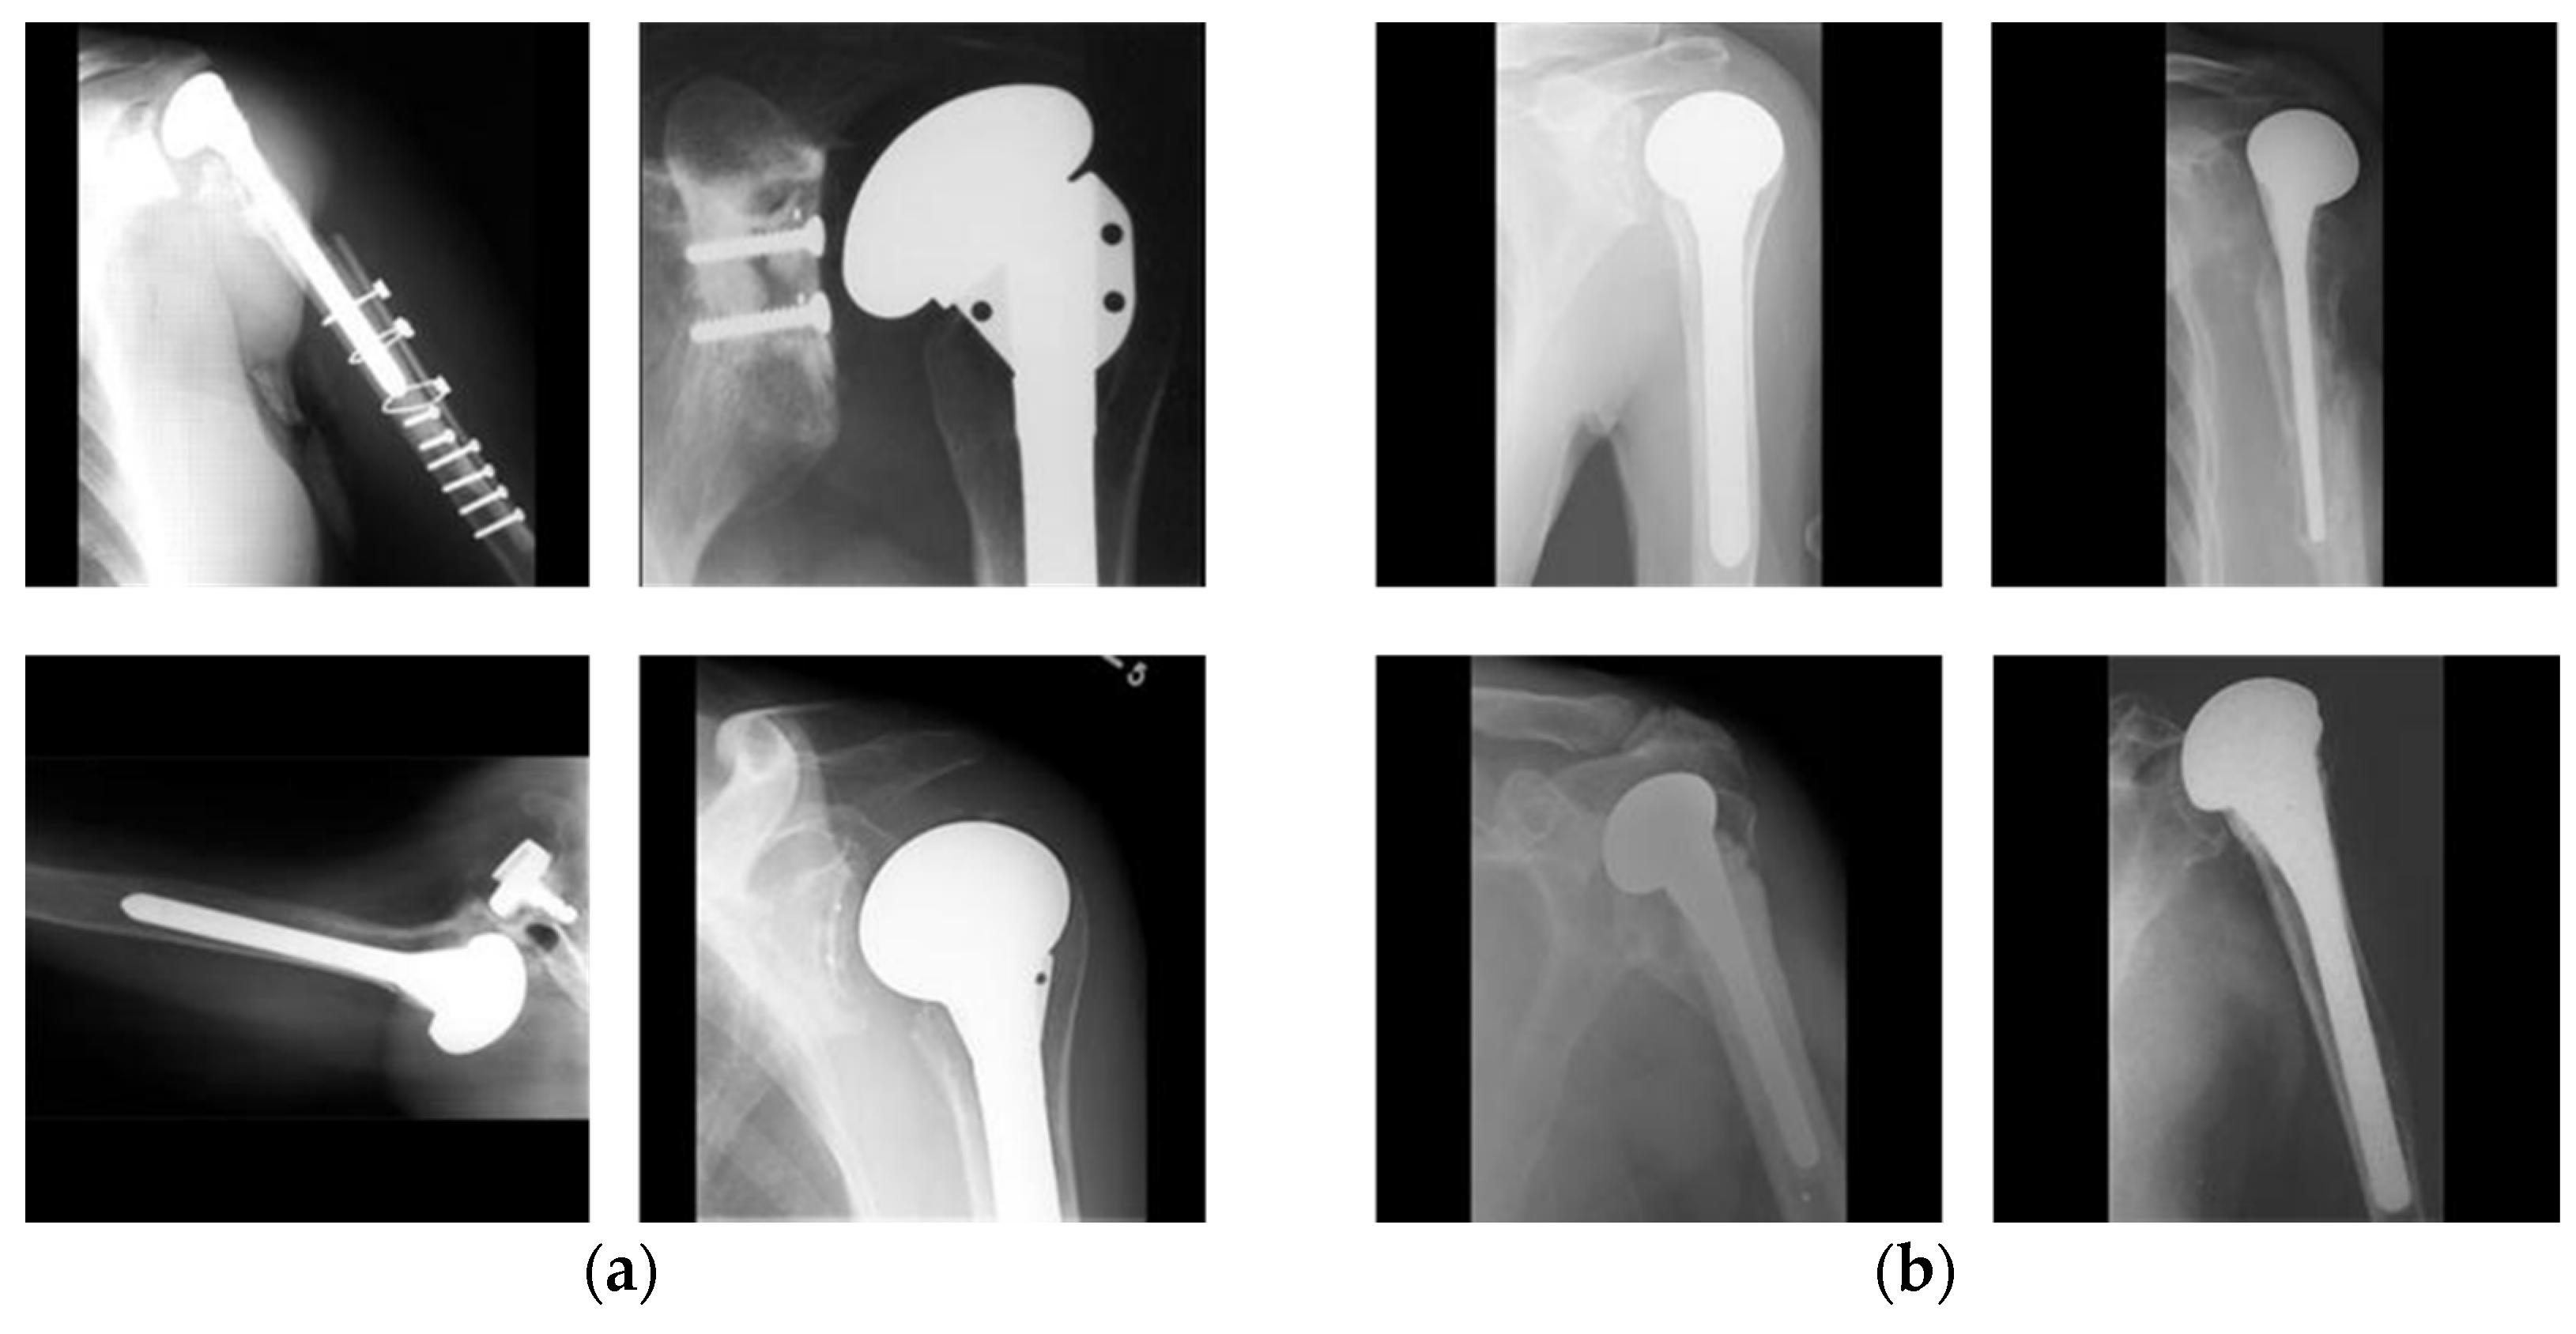

4.1. Dataset and Experimental Setups